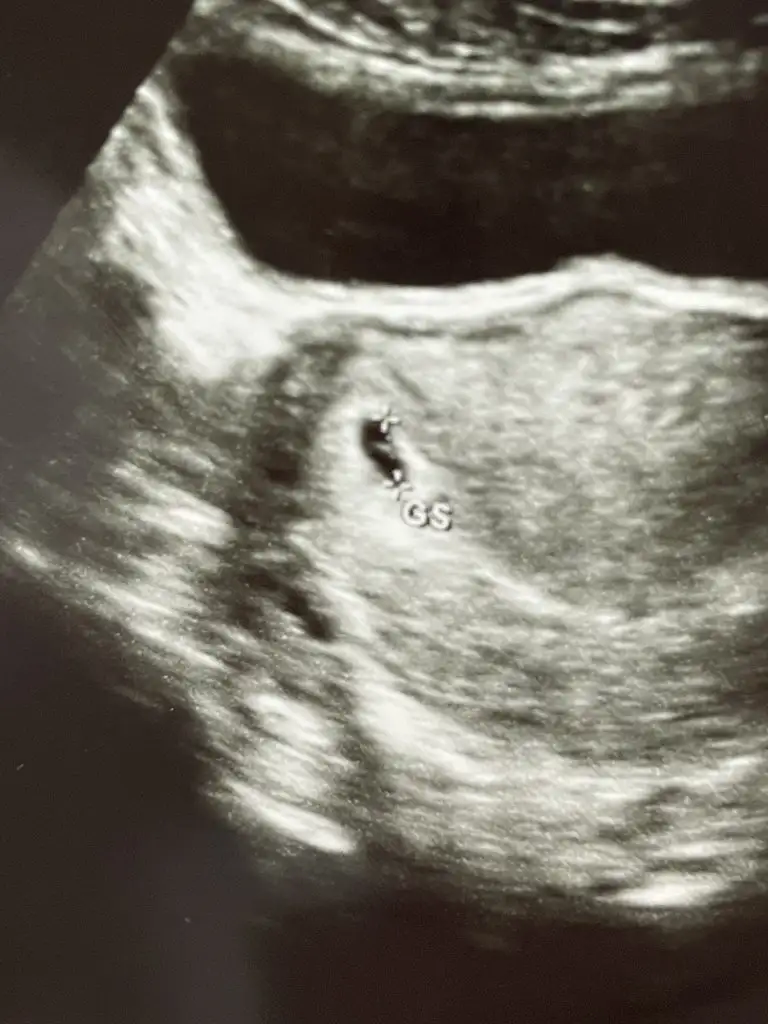

Sat 4 aralık civarı olan hamişler nasıl gidiyor, benim hafif arka yanlarım ağrıyor, sol üst bacağımın etleri ağrıyor , kasığımda mı karnımda mı bilmiyorum bi ağrı var ama adet sancısı gibi değil. Mide bulantısı var. Üşütmekten mi acaba